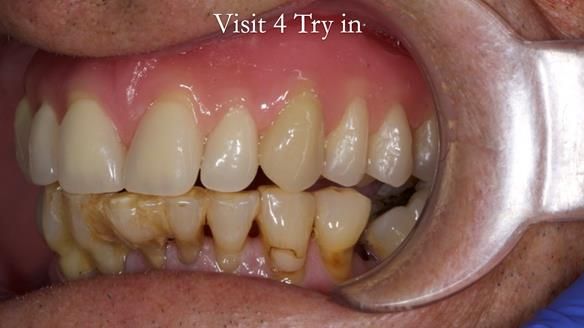

Welcome to my Newsletter 54 showing the making and fitting of dentures (a complete upper metal reinforced denture, a lower immediate partial denture and a definitive Scandinavian designed, metal based lower partial denture) for David, a 75 -year-old man. The full protocol workflow is presented including the use of dentate photographs to mimic his natural teeth.

Interestingly we found that the upper complete denture when finished and fitted didn’t have good enough retention for David’s satisfaction. It was relined by adding compound to the buccal flanges – to almost overextend into the sulcus to ‘create’ a sulcus, followed by using a light bodied silicone impression material. This improved the function of the C/-considerably. A lower Scandinavian hygienically designed lower RPD was also provided which helped with occlusal stability and reseating the upper denture – further improving the fit.